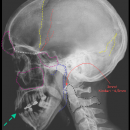

Schädel seitlich

CAVE

• Frakturnachweis (DD Suturen, Gefäßfurchen)

• Intrakranielle Luft (offene Schädelhirnverletzung)

• Frontobasis und Orbitadach

• Knöcherne Konturen der Sinus

• Spiegelbildung und/oder Verschattungen in den Sinus (Hämatosinus)

• Craniocervikaler Übergang (Abstand Atlasbogen und Dens axis) und obere HWS

• Knöcherne Konturen des Unterkiefers mit Kiefergelenk und Okklusion